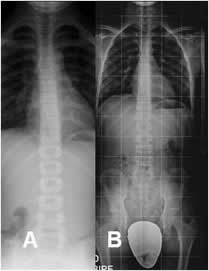

Fig 20. Radiología simple.

A: Rx AP. Proyección en chasis largo.

B: Rx telemétrica. Radiografía que permite visualizar las crestas iliacas y las cabezas femorales. En los niños se recomienda la protección gonadal, con elementos plomados.